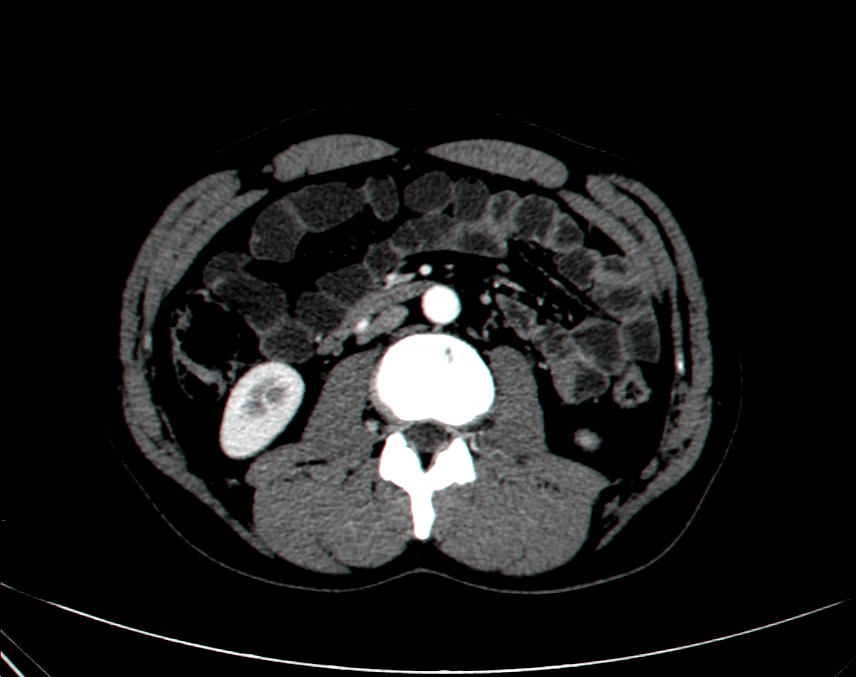

виртуальная колоноскопия - неинвазивное послойное исследование толстого кишечника с целью обнаружения в нем полипов или новообразований. Помимо кишечника, данное исследование позволяет оценить так же состояние органов брюшной полости и малого таза; для просмотра нажмите здесь

Для исследования патологии тонкого кишечника так же используется новая методика – компьютерная томография с маннитолом, позволяющая значительно повысить диагностическую ценность исследования и избавить пациента от введения зонда, сократить время обследования. , для просмотра нажмите здесь